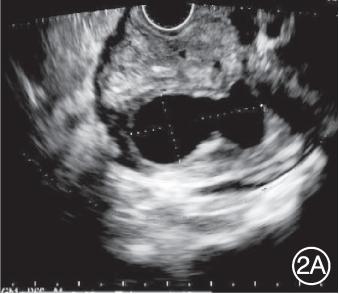

入院后完善相关实验室检查,脂肪酶284.2 U/L(参考值:13~60 U/L)、淀粉酶125.4 U/L(参考值:0~150 U/L),肿瘤标志物以及免疫球蛋白G亚型等均未见明显异常。复查超声内镜提示胰腺与十二指肠间可见一囊性病变,囊肿截面大小3.02 cm×1.46 cm,囊肿与胰管相通;胰腺钩突部胰管扩张,内可见高回声病变,伴声影;胰腺实质可见点状偏高回声;胆总管未见扩张;于囊性病变处行EUS‑FNA,抽取褐色液体2.8 mL后可见囊肿缩小(图2);随后行ERCP,在胰管内置入1枚支架。术后禁食水,给予抗炎、抑酸、抑制胰酶分泌、补液等治疗。术后6 d复查,脂肪酶122.3 U/L,淀粉酶70.2 U/L,患者腹痛及背部疼痛症状较刚入院时有明显缓解。6个月后超声内镜复查,胰管无明显扩张,其内未见高回声影(图3),行胰管支架拔除术。

2A:胰腺与十二指肠间可见一囊性病变,囊肿截面大小3.02 cm×1.46 cm,囊肿与胰管相通

2B:胰腺钩突部胰管扩张,内可见高回声病变,伴声影;2C:于囊性病变处行细针抽吸术,抽取褐色液体2.8 mL

图2 入院后复查超声内镜